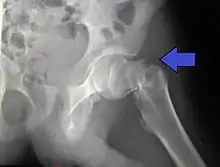

In elderly patients with displaced or intracapsular fractures surgeons may decide to perform a hemiarthroplasty, replacing the broken part of the bone with a metal implant.[38] However, in elderly people who are medically well and still active, a total hip replacement may be indicated. Independently mobile older adults with hip fractures may benefit from a total hip replacement instead of hemiarthroplasty.[39]

Traction is contraindicated in femoral neck fractures due to it affecting blood flow to the head of the femur.[40]